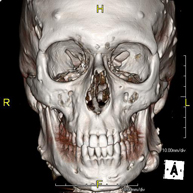

Prueba radiológica que consiste en obtener imágenes de la hipófisis cerebral de alta definición anatómica mediante el empleo de un equipo de TC (Tomografía Computarizada). Indicaciones: sospecha de tumor hipofisario, trastorno del crecimiento. - TC Macizo facial

Prueba radiológica que consiste en obtener imágenes del macizo facial (cara) de alta definición anatómica mediante el empleo de un equipo de TC (Tomografía Computarizada). Indicaciones: tumores, cirugía plástica. - TC Oídos